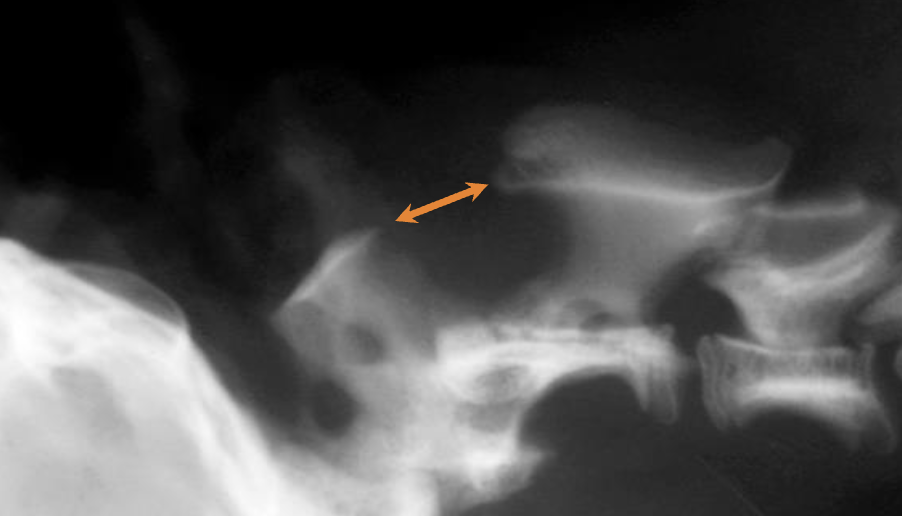

Q

AA subluxation and increased space between C1 and C2